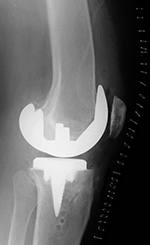

Cruciate retaining total knee prosthesis with cementless femoral and cemented tibial component and patellar resurfacing Stryker Triathlon PSC total knee arthroplasty - cruciate removal prosthesis

Cruciate retaining total knee prosthesis AP view Cruciate retaining total knee prosthesis - lateral view Stryker Triathlon total knee prosthesis Stryker Triathlon total knee prosthesis

There is a postoperative drain and skin staples. There is a posterior stabilized component (PSC) with removal of the posterior cruciate ligament. There is also a surgical drain and skin staples in place. From Taljanovic, 2005